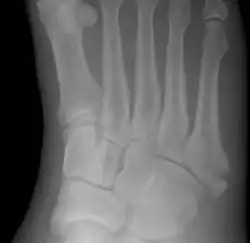

Jones fracture as seen on Xray

Diagnostic X-rays include anteroposterior, oblique, and lateral views and should be made with the foot in full flexion.

Other proximal fifth metatarsal fractures exist, although they are not as problematic as a Jones fracture. If the fracture enters the intermetatarsal joint, it is a Jones fracture. If, however, it enters the tarsometatarsal joint, then it is likely an avulsion fracture caused by pull from the fibularis brevis tendon. An avulsion fracture at the base of the fifth metatarsal is sometimes called a "dancer's fracture" or a "pseudo Jones fracture", and usually responds readily to non-operative treatment.[18] The X-ray appearance of the developmental "apophysis" in this area may have some resemblance of a fracture, but is not a fracture; it is the secondary ossification center of the metatarsal bone. It is a normal finding that occurs at this site in adolescents.[19] If an injury to that area has occurred, the physician is often able to interpret certain radiographic clues to make the differentiation. An avulsion fracture at this location is typically extra-articular and oriented transversally as compared to the longitudinal orientation of an unfused apophysis.[19]